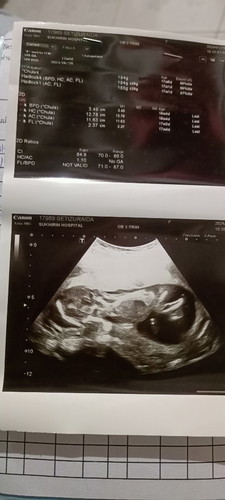

มีใครพอจะร้กูบ้างว่าลูกของเรา ชายหรือหญิงพอดีหมอเขาไม่ได้บอกอะไรเลยค่ะก็เลยไม่รู้ว่าชายหรือหญิง ภาพนี้ตอนไปเซาท์ครั้งแรง เมื่อ17w6d

หันข้างรึป่าวคะคุณแม่ ดูไม่ออกค่ะท่านี้ ต้องส่องจากก้นขึ้นไปน้า